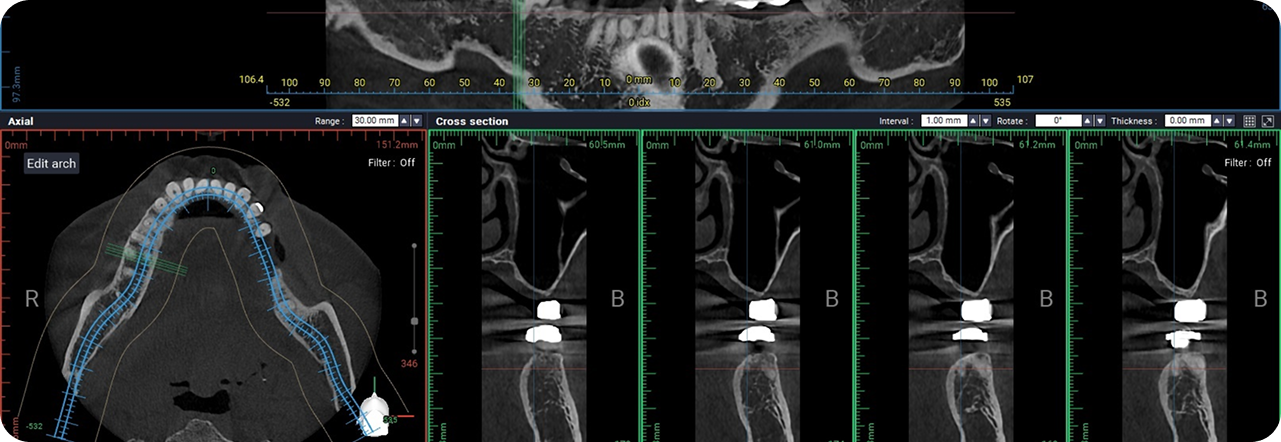

디지털 정밀 진단 기반

치료 설계

3D CT, 구강스캐너 등 정밀 진단 데이터를 기반으로

잇몸뼈 상태, 신경 위치, 교합 등, 환자 개개인의

해부학적 구조를 0.1mm 단위까지 파악하여,

안전하고 이상적인 치료 계획을 수립합니다.